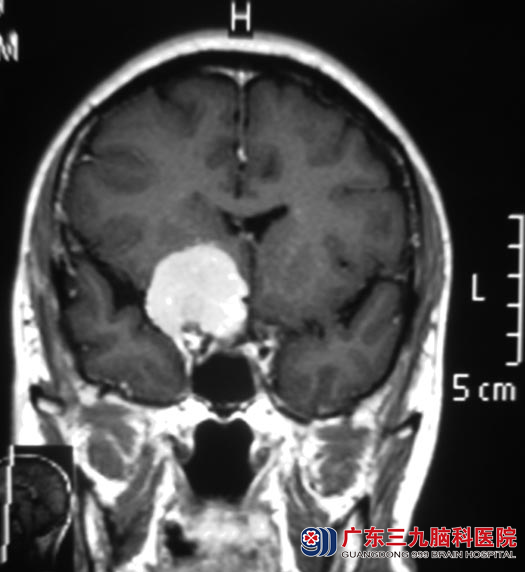

逐渐的,药物也没有效果,同时伴有额颞部间断性疼痛。当地医院行头颅CT检查提示:右侧鞍旁占位,考虑脑肿瘤。广东三九脑科医院头颅MR检查提示“右侧蝶骨嵴脑膜瘤,大小约3.1cm×3.1cm×3.5cm,考虑脑膜瘤”,CTA示“右侧颈内动脉及其分支与肿瘤关系密切”。

完善相关检查后,综合神经外科 鲁明主任主刀,在全麻下行右侧蝶骨嵴脑膜瘤切除术,术中见灰白色肿瘤位于右侧鞍旁蝶骨嵴区,颈内动脉位于肿瘤下方,大脑中动脉位于肿瘤后下方,大脑前动脉位于肿瘤内侧下方,在显微镜下分块全切肿瘤,术中视神经、动眼神经、颈内动脉及其分支血管保护完好。手术的谭老师头不痛了,睡眠基本恢复如前。